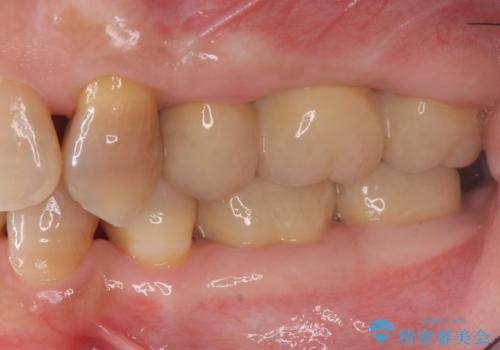

においやぐらつきなどの深い症状がなくなり、しっかりと噛めるようになった!と喜んでいただくことができました。